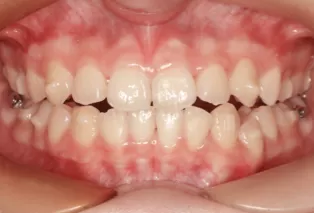

Photos intra-orales